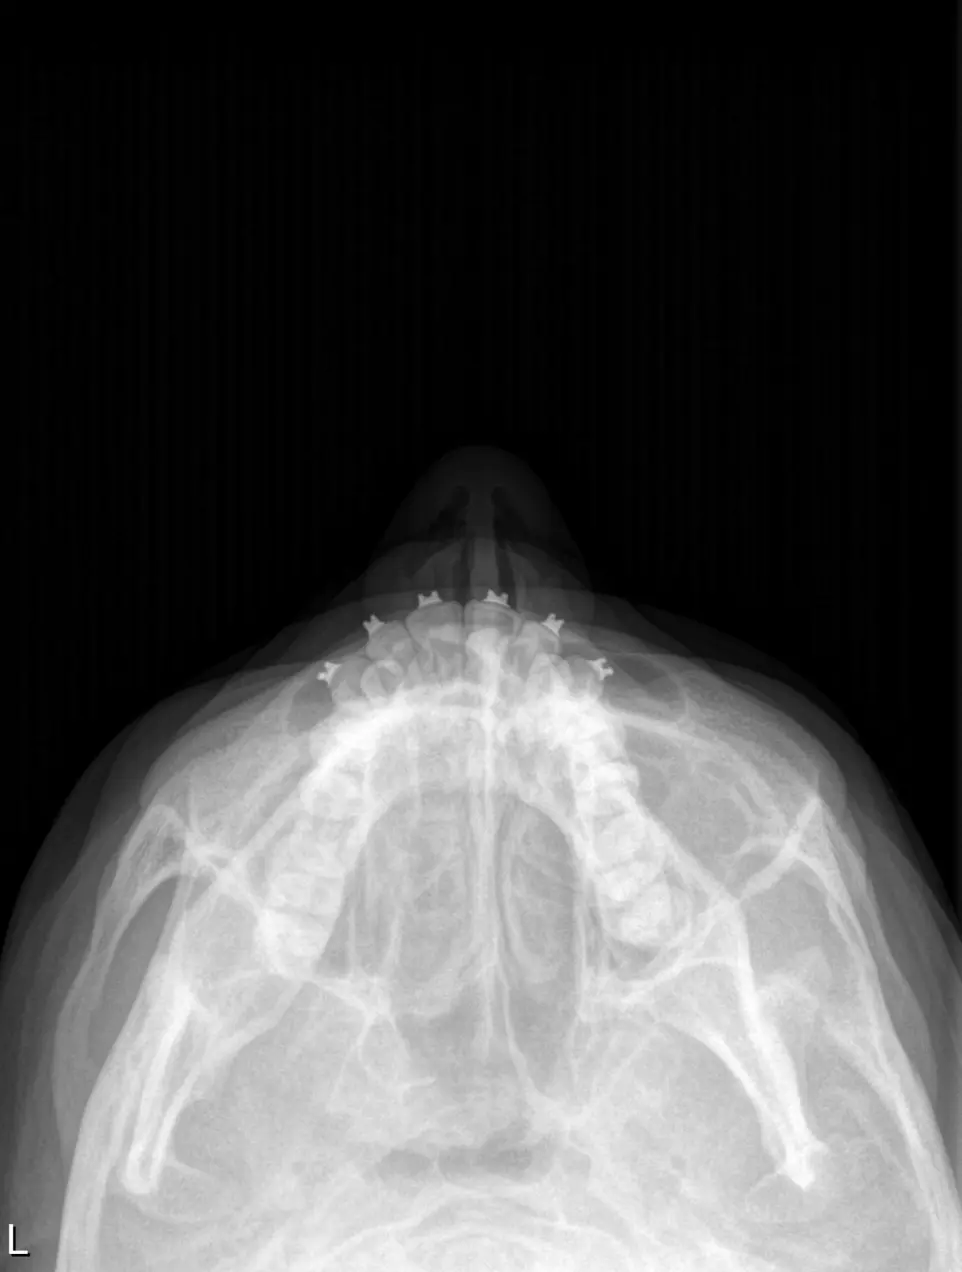

RX ANTEROPOSTERIOR

Nos permite visualizar las estructuras anatómicas en su eje frontal, evaluando su alineación, forma, tamaño y relaciones óseas. Utilizandose para, identificar fracturas, deformaciones o lesiones óseas, evaluar articulaciones y estructuras anatómicas